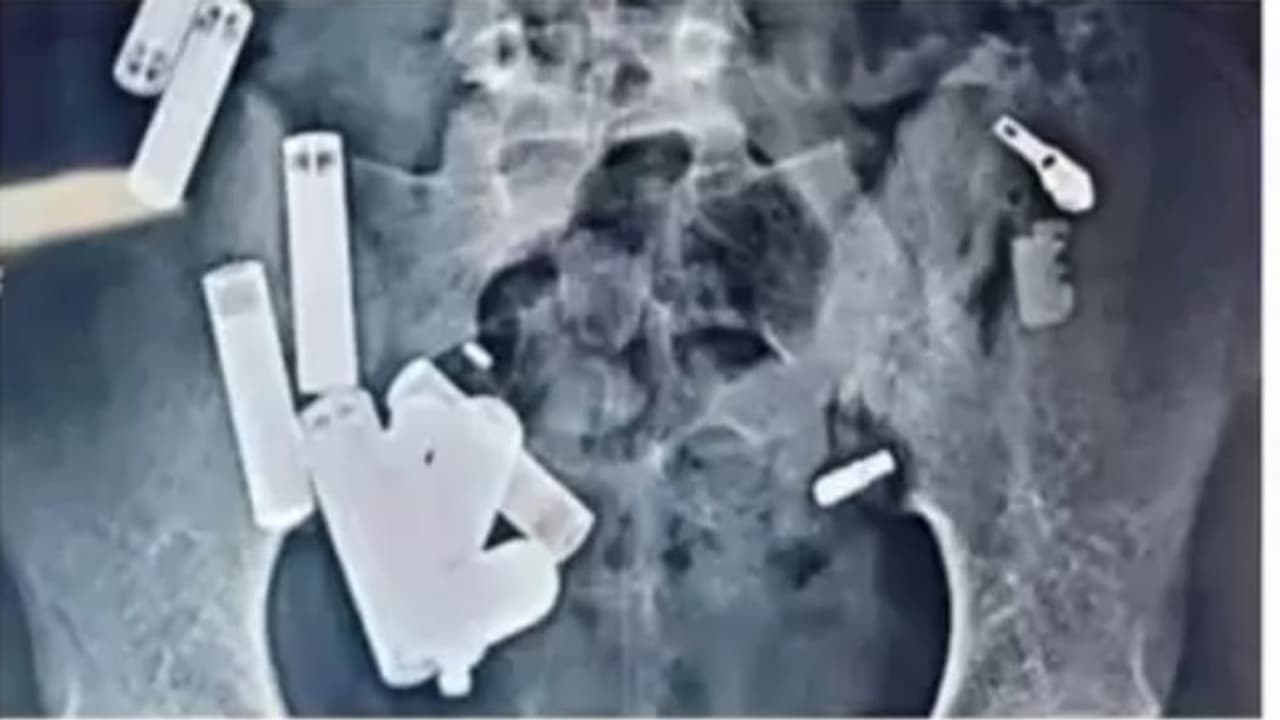

उत्तर प्रदेश के हाथरस के 14 वर्षीय लड़के की दिल्ली के सफदरजंग अस्पताल में डॉक्टरों द्वारा पांच घंटे की जटिल सर्जरी के बाद मौत हो गई। डॉक्टरों ने उसके पेट से 65 वस्तुएं निकालीं, जिसमें बैटरी, चेन, रेजर ब्लेड के टुकड़े और स्क्रू शामिल थे।

आगरा। उत्तर प्रदेश के हाथरस से 14 वर्षीय आदित्य शर्मा की दर्दनाक मौत ने सबको झकझोर दिया है। दिल्ली के सफदरजंग अस्पताल में डॉक्टरों ने आदित्य के पेट से पांच घंटे की जटिल सर्जरी में 65 वस्तुएं निकालीं, जिनमें बैटरी, चेन, रेजर, ब्लेड के टुकड़े और स्क्रू शामिल थे। हालांकि, सर्जरी के बाद भी डॉक्टर उसे बचा नहीं पाए, और उसकी मौत संक्रमण के कारण हुई।

आगरा में इलाज के बाद आदित्य को जयपुर के अस्पताल रेफर किया गया था, जहां कई टेस्ट और स्कैन के बाद उसे वापस यूपी भेजा गया। दो दिन बाद फिर उसकी तबीयत बिगड़ने पर उसे अलीगढ़ के अस्पताल ले जाया गया। वहां डॉक्टरों ने उसके नाक की रुकावट को सफलतापूर्वक हटाया, लेकिन उसके पेट में असामान्य दर्द होने पर 26 अक्टूबर को व्यापक अल्ट्रासाउंड किया गया। इस टेस्ट में 19 अज्ञात वस्तुएं दिखीं, जिसे देख डॉक्टरों ने तत्काल नोएडा के अस्पताल में रेफर कर दिया।

पेट से निकाली गईं 65 वस्तुएं

नोएडा में डॉक्टरों ने जांच के दौरान उसके पेट में 42 वस्तुएं और पाईं, जिससे तुरंत उसे दिल्ली के सफदरजंग अस्पताल ले जाया गया। वहां डॉक्टरों ने स्कैन में "कुल 65 वस्तुएं" पाईं और इस स्थिति में उसकी हृदय गति 280 प्रति मिनट तक पहुंच गई थी। पांच घंटे की सर्जरी के बाद भी डॉक्टर उसे नहीं बचा सके और उसकी दर्दनाक मौत हो गई।